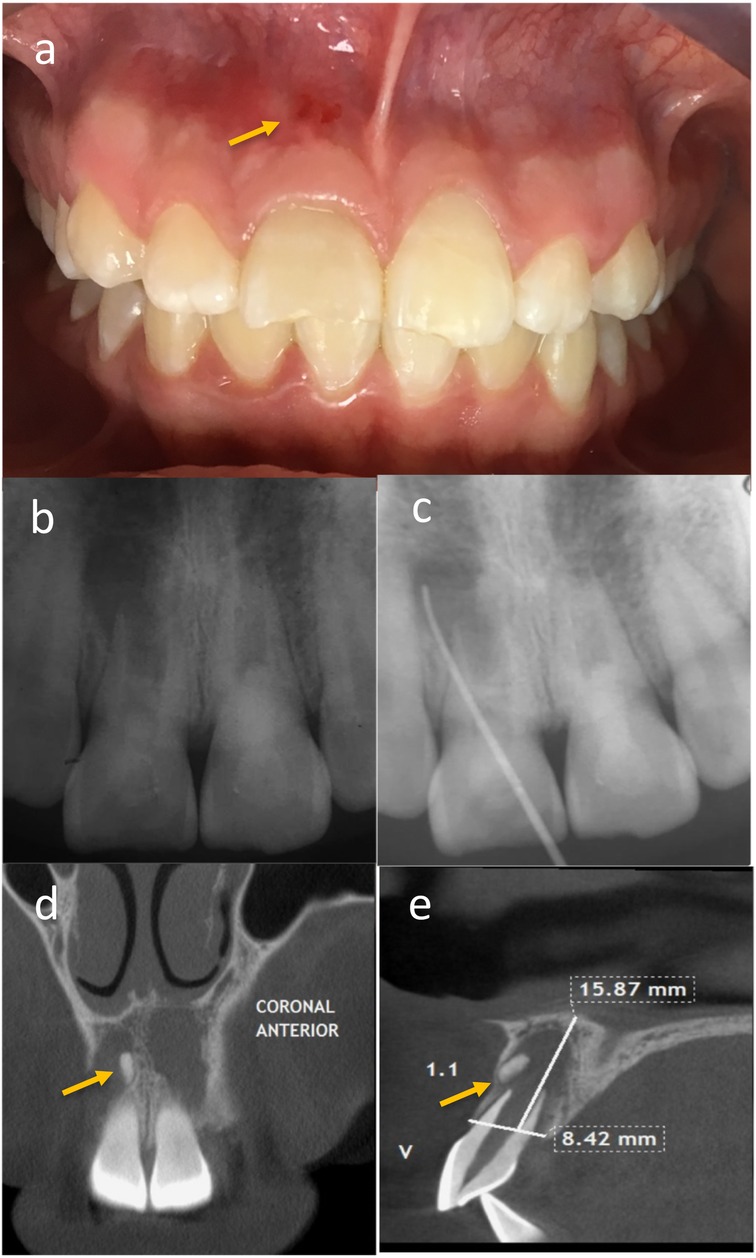

One month after both RE sessions, the patient returned to the scheduled control with severe pain in tooth 1.1 that had begun two weeks earlier. Clinical examination revealed an erythematous area in the mucosa of tooth 1.1, with pain to percussion and palpation of the vestibular fold (Figure 3a). A control radiograph was taken, and observation continued (Figure 3b). A composite restoration was placed on tooth 2.1.

Composite image showing multiple dental examinations. Panel (a) displays an intraoral view of a patient's teeth with an arrow indicating an area of interest. Panel (b) is a dental X-ray showing front teeth. Panel (c) depicts a periapical X-ray with a probing line. Panel (d) shows a coronal CT section of the anterior teeth, highlighted by an arrow. Panel (e) is a sagittal CT scan with measurements of 15.87 millimeters and 8.42 millimeters marked, with an arrow pointing to a specific region.

Figure 3. (a) Patient reported severe pain in tooth 1.1, and clinically, an erythematous area in the mucosa with pain on percussion and palpation of the vestibular fold was found. (b) A control radiograph was taken and the patient was maintained under observation. (c) An active sinus tract related to tooth 1.1 was observed, and fistula catheterization was performed. (d,e) A possible dental formation associated with tooth 1.1.

At the subsequent follow-up, one month later, the patient was asymptomatic to percussion and palpation in both teeth. However, an active sinus tract related to tooth 1.1 was observed, so fistula catheterization was performed (Figure 3c), and a review of the initial Cone beam computed tomography (CBCT) detected a possible bone fragment associated with this tooth (Figures 3d,e). The patient remained under observation.

Another month later, the decision was made to refer the patient for surgical removal of the suspected bone remnant. An oral and maxillofacial surgeon performed the surgical procedure three months later. After the surgery, an acute apical abscess (stage 3) was reported, and subsequent controls showed the persistence of the sinus tract. Clinical examination revealed continued symptomatic percussion and palpation of the vestibular fold, with an active sinus tract related to tooth 1.1. The infection was controlled with 5.25% NaOCl irrigation and intracanal medication with calcium hydroxide paste (UltraCal XS, Ultradent Products, Inc., South Jordan, UT, USA). Given the likely absence of apical papilla cells due to the surgeon's curettage, apexification was initiated (Figure 2a).